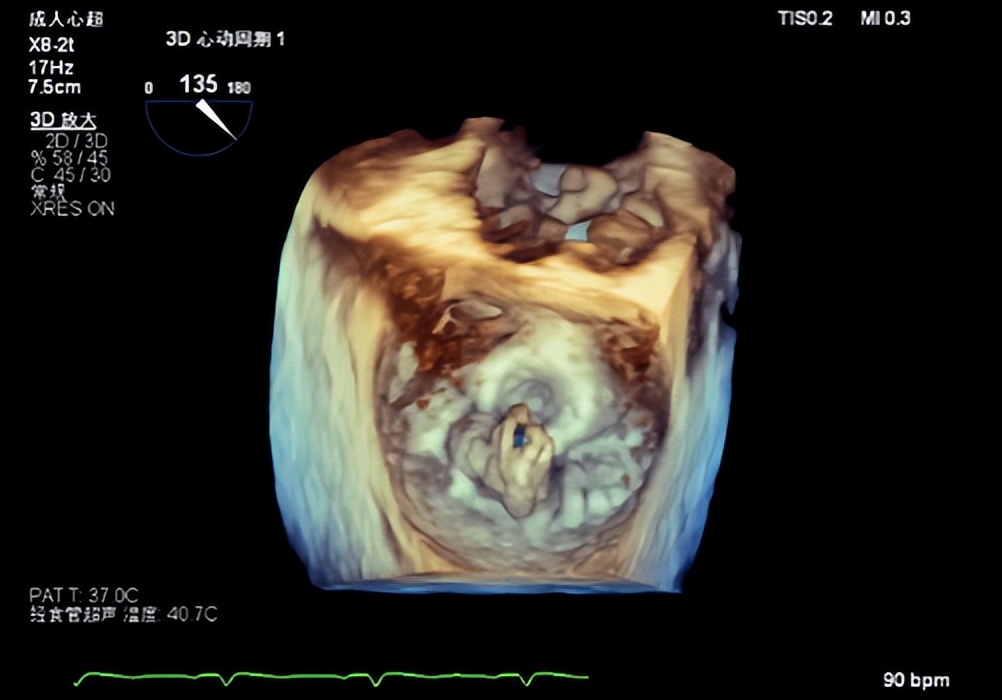

图三(3D示后叶脱垂伴重度关闭不全)

食道超声显示术后即刻效果显著,心房侧未见返流信号(图九),3D显示二尖瓣呈组织桥形态良好的双孔状,返流消失(图十),临床症状明显改善,术后效果堪称完美。

图十(左:术前食道3D示4+大量返流;右:术后二尖瓣呈组织桥形态良好的双孔状,返流消失)